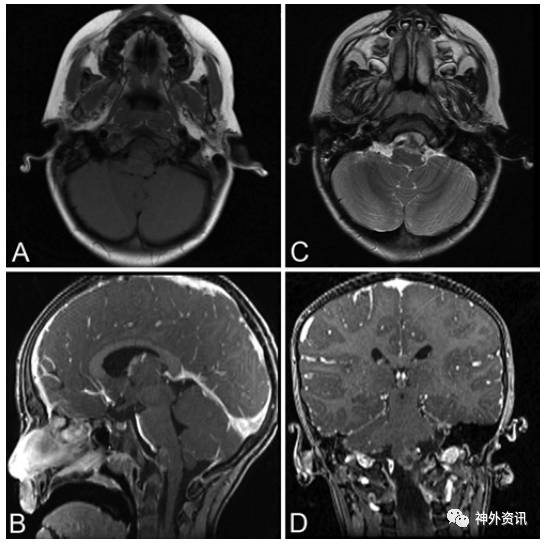

5岁男性患儿,诊断为斜坡脊索瘤(图1)。5年前行经口入路完全切除肿瘤(图2),术后进行质子束放疗。病理学检查报告为典型的脊索瘤,免疫组化提示角蛋白强阳性、上皮膜抗原强阳性、S-100免疫反应阴性和MIB-1标记指数为10%(图3)。术后因脑脊液漏反复出现脑膜炎,给予抗生素治疗后好转。接着继发交通性脑积水,通过脑脊液VP分流术降颅内压。术后5年发现肺部结节(图4),手术活检提示为低分化的脊索瘤,免疫组化结果和原发部位脊索瘤相似,即角蛋白强阳性和上皮膜抗原强阳性(图5),表明斜坡脊索瘤颅外转移。随后相继发生胸壁和颅骨转移。由于大部分脊索瘤mTOR通路激活,所以给患者使用伊马替尼联合雷帕霉素化疗后,肿瘤缩小,疼痛有所减轻。但是,9月后出现额部头皮肿物,并导致附近的VP分流管周围皮肤破溃。遂行头皮肿物切除和皮瓣转移术,以防止分流管暴露。免疫组化提示PD-L1高表达,即行PD-L1单抗治疗,胸痛明显缓解。6月后又出现新发的肺部转移灶,疼痛明显。免疫组化和基因检测为INI-1缺失,应用EZH2进行晚期解救治疗,疗效尚待评价。

图2. 术后MRI显示斜坡脊索瘤全切除。